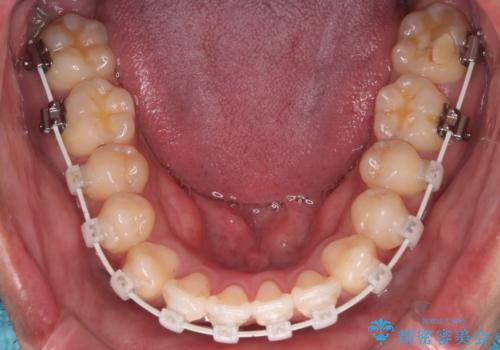

- 矯正装置

- 審美装置

IPR(歯と歯の間を削る処置)と顎間ゴムを行い歯並びを整える治療計画を立てました。

早く終わらせたいとの事でしたが、ゴム掛けを頑張っていただいたので

9ヶ月という短い期間で治療が完了しました。

矯正後は保定経過とメンテナンスで経過を見ていきます。